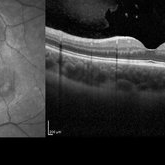

Diabetic Macular Edema

May 28 2016 by Olivia Rainey

Optical coherence tomography of an 54-year-old female with diabetic macular edema affecting both eyes. Patient has a history of proliferative diabetic retinopathy s/p PRP/PPV/MP/EL, and glaucoma s/p tube shunt in both eyes. There has been a persistence of her macular edema and limited response to antiVEGF therapy, which puts into question whether there is another cause for her edema. Leading the possible causes is her renal insufficiency and fluid retention. Patient was seeing 20/50 in the right eye and 20/80 in the left eye.

Photographer: Olivia Rainey

Imaging device: Heidelberg Spectralis

Condition/keywords: anti-VEGF, diabetic macular edema, edema, glaucoma, optical coherence tomography (OCT), pan-retinal photocoagulation (PRP), proliferative diabetic retinopathy (PDR)